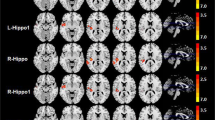

Head motion during scanning did not differ significantly between groups (p > 0.121), and mean displacements were small (mean absolute displacement: 0.2502 ± 0.1479 mm). Whole-brain dFC was significantly different from that calculated from the randomized time series (t(100) = 2.583, p = 0.011), suggesting variability reflects brain dynamics rather than measurement noise. Mixed ANOVAs showed no significant differences in DMN-dFC or FPN-dFC between groups or over time (p > 0.151) (Fig. 2).

Dynamic functional connectivity. Distributions of dynamic connectivity of the default mode network (DMN-dFC, A) and frontoparietal network (FPN-dFC, B) are visualized at baseline (BL) and follow-up (FU) separately for women with BC treated with chemotherapy (BCC +), not treated with chemotherapy (BCC-), and no-cancer controls (NC). No statistically significant differences were found between groups or over time